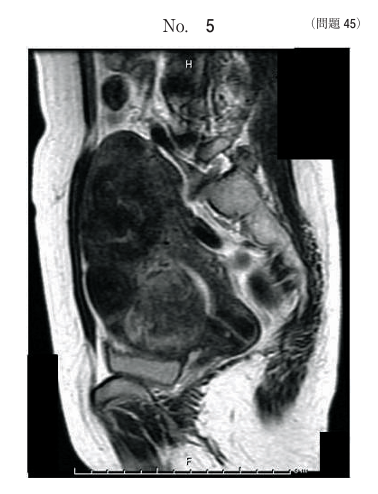

午前/問題45

女性骨盤のMR像で描出されている病変はどれか。

1.腟癌

2.膀胱癌

3.直腸癌

4.子宮筋腫

5.子宮頸癌